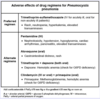

Indications for corticosteroid use in Pneumocystis pneumonia treatment (in addition to TMP-SMX) include PaO2 […] mmHg.

Indications for corticosteroid use in Pneumocystis pneumonia treatment (in addition to TMP-SMX) include PaO2 < 70mmHg or A-a gradient > 35 mmHg.

also indicated if SaO2 < 92%